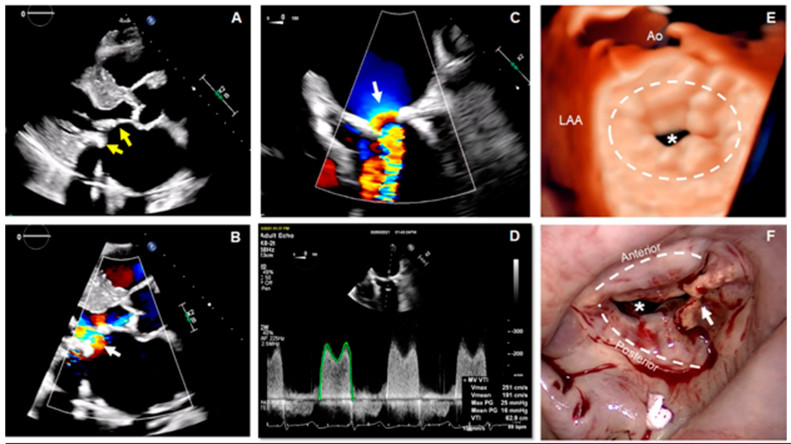

Un hombre de 63 años con antecedentes de insuficiencia renal terminal (IRT), hemodiálisis de larga duración y accidente cerebrovascular 2 años antes e insuficiencia cardíaca con fracción de eyección conservada, un año antes. En la actualidad, presenta disnea progresiva y tos seca. Se realizaron ETT y ETE.

En la vista en eje largo paraesternal del ETT se observa la aurícula izquierda (AI) muy dilatada y calcificación del anillo mitral (CAM) grave, que afecta las partes anterior y posterior del mismo (Fig. 2A, flechas amarillas). En esta misma vista de la ecografía Doppler color se detecta aceleración del flujo hacia el orificio de la VM (Fig. 2B, flecha blanca). Esto se corrobora posteriormente en las imágenes de la ETE, donde la convergencia del flujo hacia el orificio de la VM muestra una gran área de superficie de isovelocidad proximal (PISA) en la vista medioesofágica de 4 cámaras (Fig. 2C, flecha blanca). Estos hallazgos y la presencia de un gradiente medio de la VM de 16 mmHg en la ecografía Doppler de onda pulsada (Fig. 2D) son compatibles con estenosis mitral (EM) grave. En la vista frontal 3D ampliada de la VM se puede observar la distribución circunferencial de la CAM (Fig. 2E, línea blanca discontinua) y el tamaño extremadamente reducido del orificio de la VM en la fase inicial-media de la diástole (asterisco blanco). En la Fig. 2F se evidencia la correlación sólida entre los hallazgos quirúrgicos y las imágenes ecocardiográficas, según se aprecia a través la CAM extendida hacia delante y atrás (líneas blancas discontinuas), la afectación de las comisuras (flecha blanca) y la estenosis grave del orificio de la VM (asterisco blanco).

Objetivos de aprendizaje: La CAM es un proceso crónico, degenerativo y metabólicamente regulado que da lugar al depósito de calcio, sobre todo en la parte posterior del anillo, y se relaciona no solo con el estrés hemodinámico, sino también con la inflamación, los lípidos y la alteración del metabolismo óseo y mineral. (6 Su prevalencia varía del 5% al 42% en función de la modalidad de obtención de imágenes utilizada, las características de la población estudiada y sus factores de riesgo asociados. (7 Los pacientes con IRT tienen, en particular, alto riesgo de CAM 7. Se ha demostrado que esta enfermedad se asocia de forma independiente con mortalidad cardiovascular y por cualquier causa, accidente cerebrovascular y arritmias (específicamente fibrilación auricular). 7 Aunque se detecta con frecuencia mediante ETT y ETE, la tomografía cardíaca es útil para calificar y cuantificar la densidad, gravedad y extensión de la CAM y su relación con otras estructuras cardíacas. 6 Las opciones de tratamiento médico son limitadas. La cirugía (reparación o reemplazo) puede constituir un reto, ya que suele requerir un tiempo quirúrgico prolongado para la descalcificación y reconstrucción de la VM.